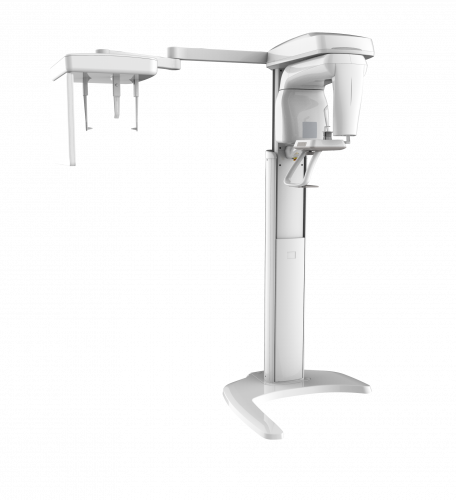

| TYPE | TOP VIEW | FRONT VIEW |

|---|---|---|

|

PaX-i (Pano) |

|

|

|

PaX-i SC (Pano/Scan Ceph) |

|

|